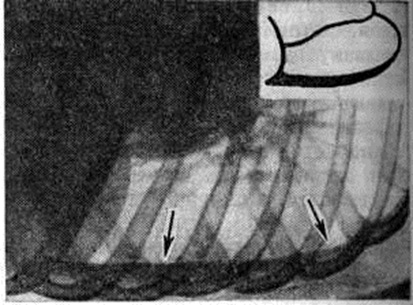

При накоплении больших количеств жидкости, когда последняя не умещается между висцеральной и диафрагмальной плеврой, она переходит в плевральные синусы. В этих случаях количество жидкости в плевральной полости обычно превышает 500 миллилитров чем выше расположена граница выпота, тем это количество больше. При переводе больного в горизонтальное положение жидкость растекается и прозрачность соответствующего лёгочного поля представляется пониженной, это так называемый феномен Ленка (смотри полный свод знаний Ленка феномен). Однако при небольшом количестве жидкости (менее 400 миллилитров) перевод больного в горизонтальное положение на трохоскопе не всегда позволяет получить положительный феномен Ленка, так как толщина слоя жидкости, растекающейся вдоль всей задней стенки грудной клетки, бывает недостаточной для того, чтобы появилась разница в прозрачности лёгочных полей. Лучшим способом выявления выпота в плевральной полости является исследование в латеропозиции на соответствующем боку. При этом жидкость растекается вдоль рёберного края, и по ширине образовавшейся пристеночной лентовидной тени можно судить о количестве выпота (рисунок 3). Если жидкости мало, целесообразно производить снимок в фазе выдоха; при этом полоска затемнения становится шире вследствие подъёма купола диафрагмы. Накопление очень большого количества жидкости в плевральной полости приводит к массивному затемнению всего лёгочного поля («тотальный плеврит») и резкому смещению срединной тени в противоположную сторону (рисунок 4).

Рис. 3.

Латерограмма больного с левосторонним плевритом: выпот образует пристеночную лентовидную тень (указана стрелками).